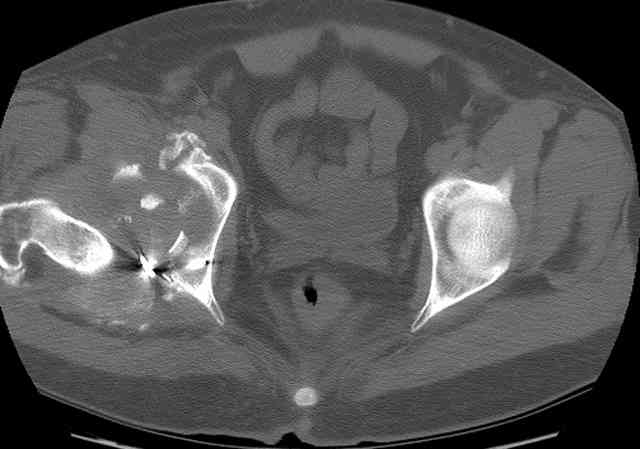

I'll include a few images of a similar injury in a similarly large male patient. This patient "showed up" in our ER c/o hip pain 2 months after being treated in the lateral position, without a quality reduction, without an anterior column transverse supporting implant, with an unbalanced plate applied too medially, with insufficient caudal segment fixation...it took over 8 hours and a 3+ l blood loss to debride the callus from front then

back, excise the HO, release his sciatic nerve, reduce the head-transverse-wall, and fix it...and now it's a staging procedure.